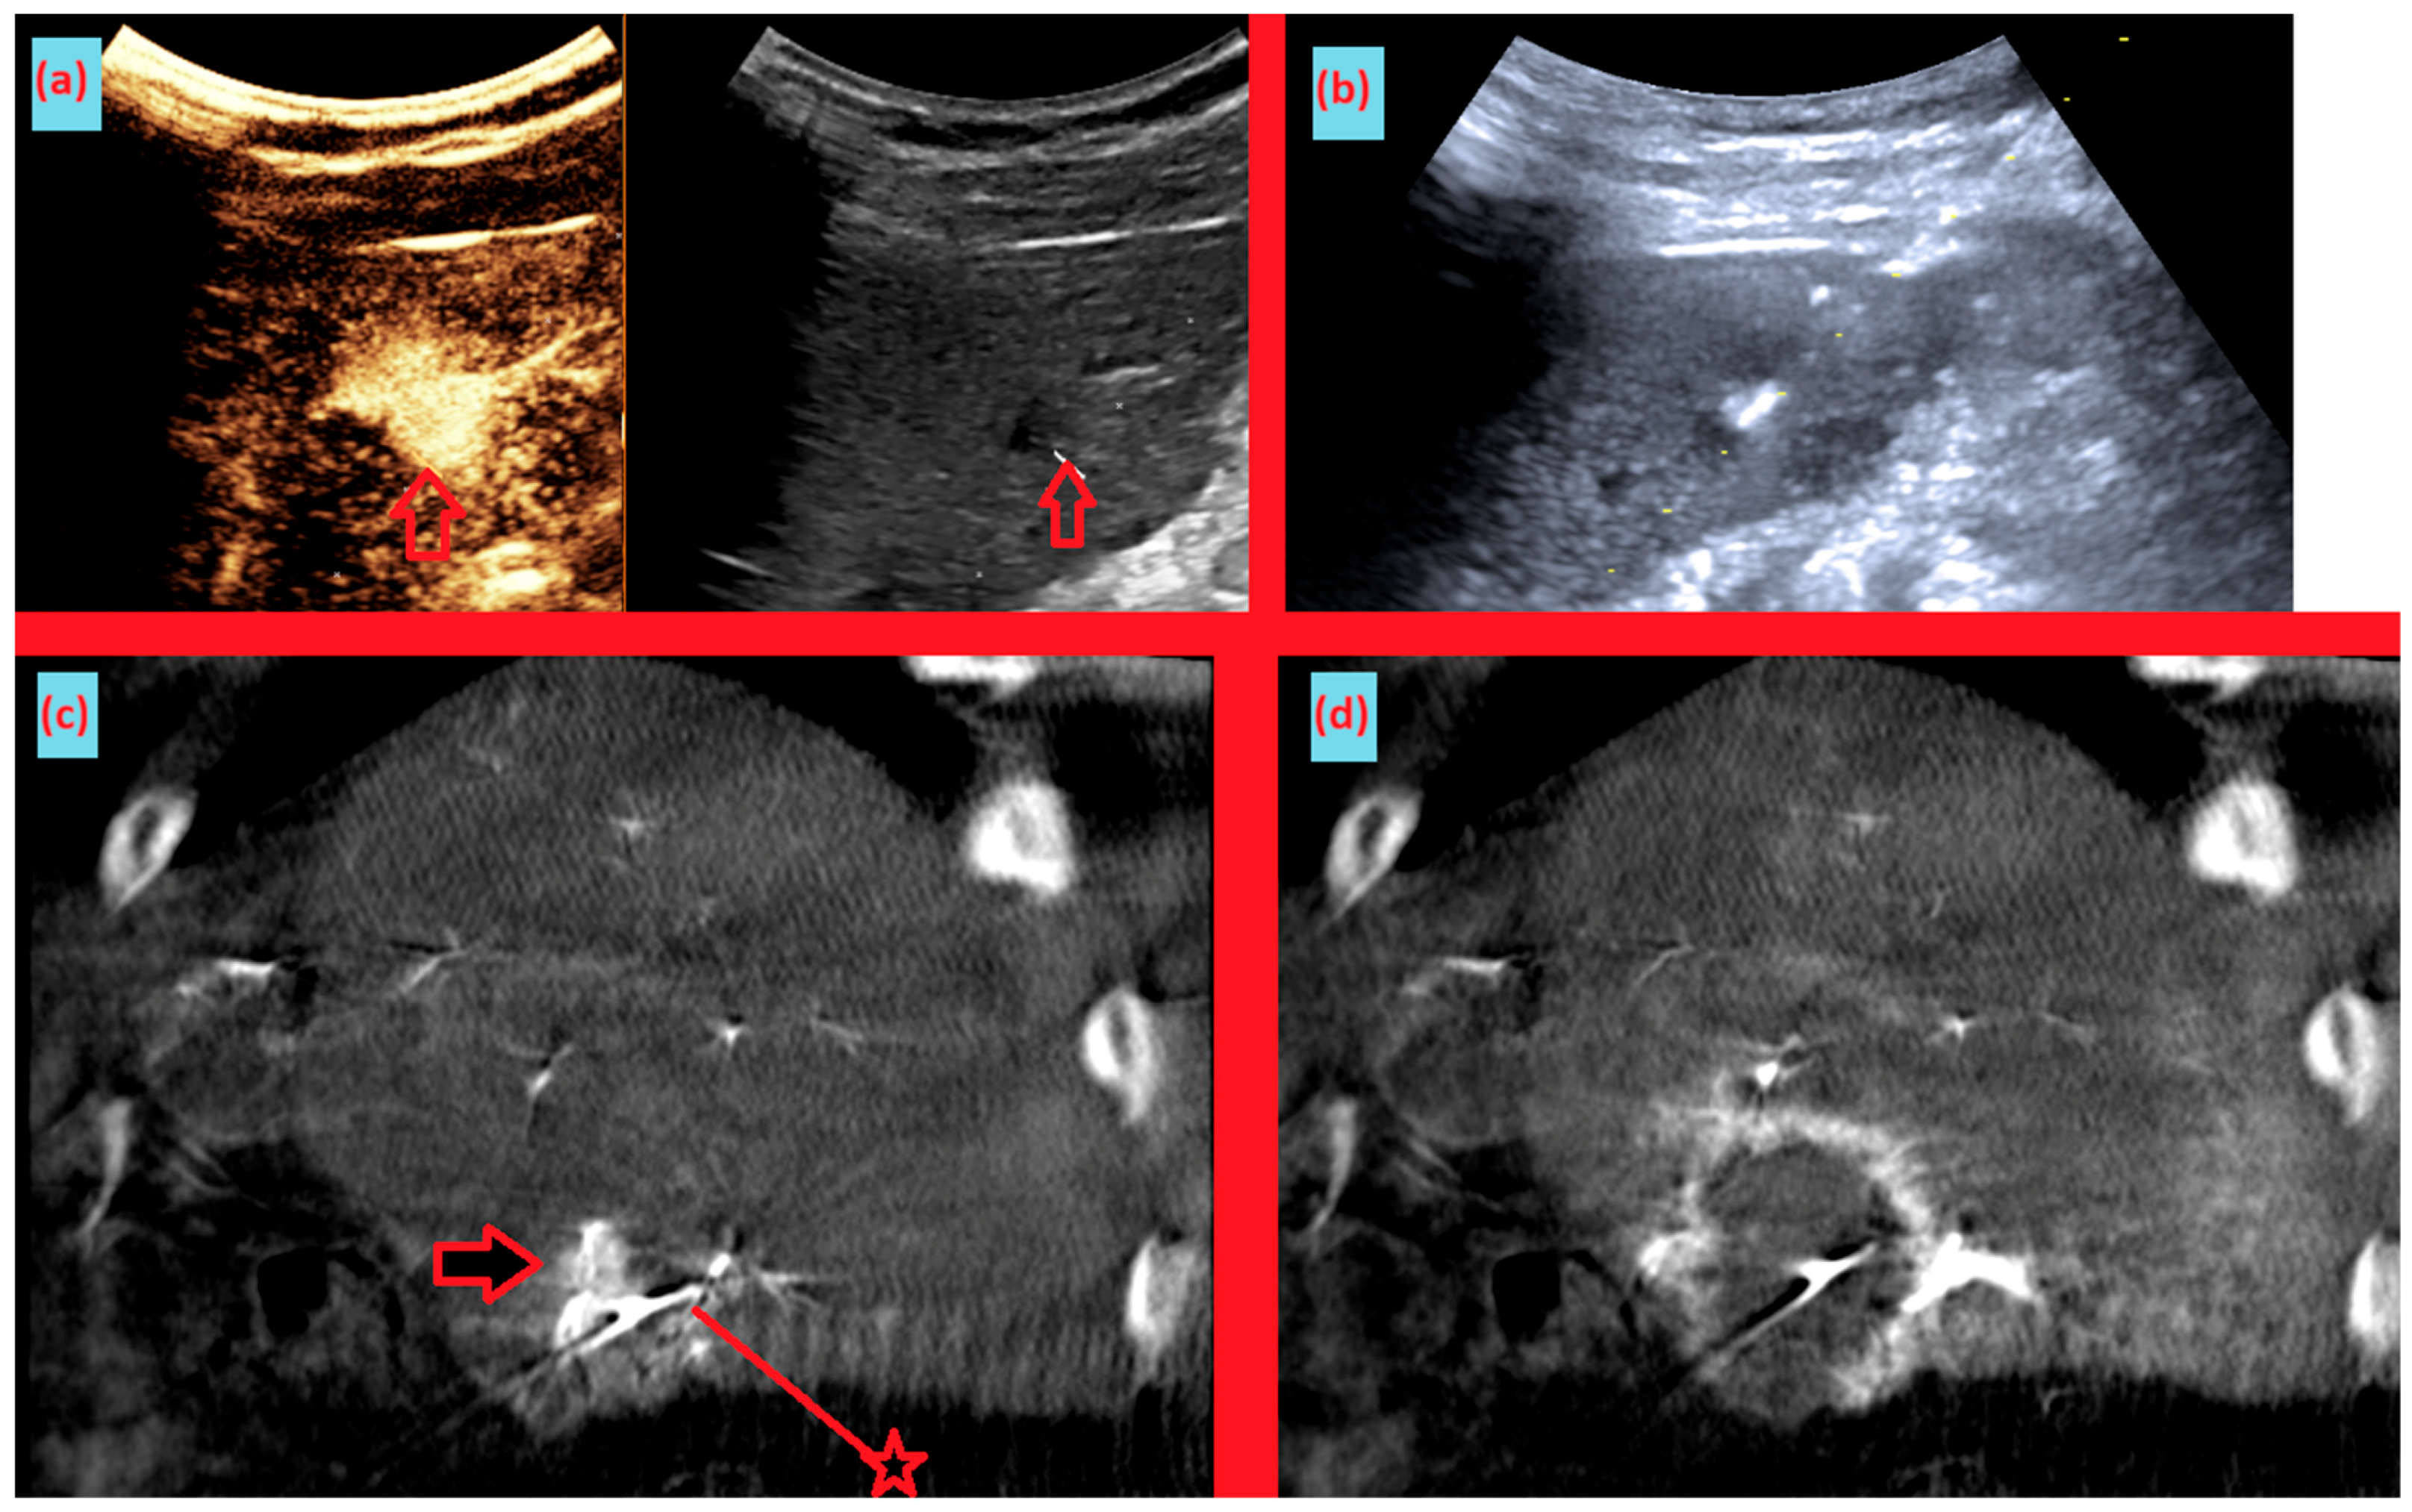

Figure 5. Images from another patient with hepatocellular carcinoma undergoing angio CBCT-guided RFA. (a) Pre-ablation CEUS and B-mode ultrasound demonstrating discordance between the CEUS-enhancing area and the hypoechoic lesion on B-mode. (arrow = mass) (b) During RFA, ultrasound-guided needle insertion was performed, targeting the hypoechoic lesion on B-mode. (c) Sagittal reformatted angio CBCT obtained after the initial needle placement shows the needle positioned inferior to the enhancing tumor. After review, the needle was repositioned slightly superiorly. (arrow = mass, line with star = RFA needle) (d) Sagittal reformatted angio CBCT after ablation demonstrates an adequate ablation zone with complete loss of lesion enhancement, consistent with complete ablation.

As shown in Figure 1, angio-CBCT allows for higher visibility of the target mass, as reflected in the ΔHU values. This can be visually confirmed in several cases. Representative cases in Figure 2 and Figure 3 demonstrate how the target mass is much more conspicuous to the operator on angio-CBCT compared to pre-procedural CT. In Figure 4, a mass, which was nearly invisible on pre-procedural CT, was identified through angio-CBCT, aiding the targeting process. Figure 5 shows a case where a mass with discordance between USG and CEUS was confirmed using angio-CBCT, leading to needle repositioning and achieving complete ablation. Finally, Figure 6 illustrates a case where a residual tumor was identified on angio-CBCT and re-ablation resulted in complete ablation.